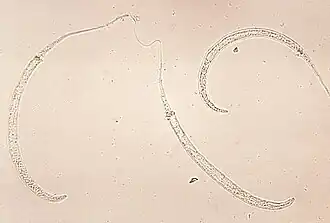

Dracunculus medinensis, comummente conhecido como verme-da-guiné[1][2], é uma espécie de nemátodo da família Dracunculidae. As fêmeas da espécie parasitam seres humanos, causando a dracunculíase[3] (trambém grafada dracunculose).[4]

O Dracunculus medinensis "é um filarídeo do tecido subcutâneo humano, encontrado na África e Ásia. No tempo da escravidão ocorreu um foco em Feira de Santana (BA), extinto posteriormente",[8] conhecido também como filária de Medina, é o maior dos parasitos teciduais que afetam o ser humano.

"A fêmea adulta, que pode carregar de um a três milhões de embriões ou microfilária, mede em torno de 100 cm de comprimento e 2mm de largura e o macho, aproximadamente 5 cm.[1] Os vermes se localizam nas pernas, mas podem ser encontrados em outras partes do corpo que, com frequência entram em contado com a água.[1] Quando as fêmeas estão grávidas, deixam o tecido subcutâneo do hospedeiro e migram para o derma, onde formam uma pápula, que se torna vesiculada e finalmente se rompe, causando uma úlcera. Na ocasião em que o hospedeiro humano, com esta vesícula rompida entra na água, a fêmea do parasito exterioriza sua cabeça e a porção anterior do corpo, onde se encontra o útero, este forma uma hérnia que, em contato com a água se rompe e libera os embriões".[8]